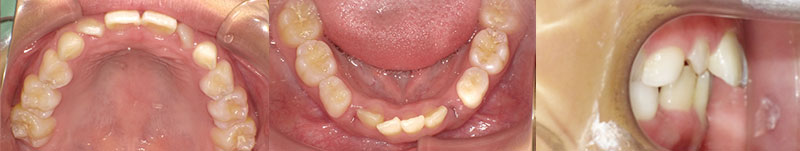

| 初診時口腔内写真 |

|---|

![]() |